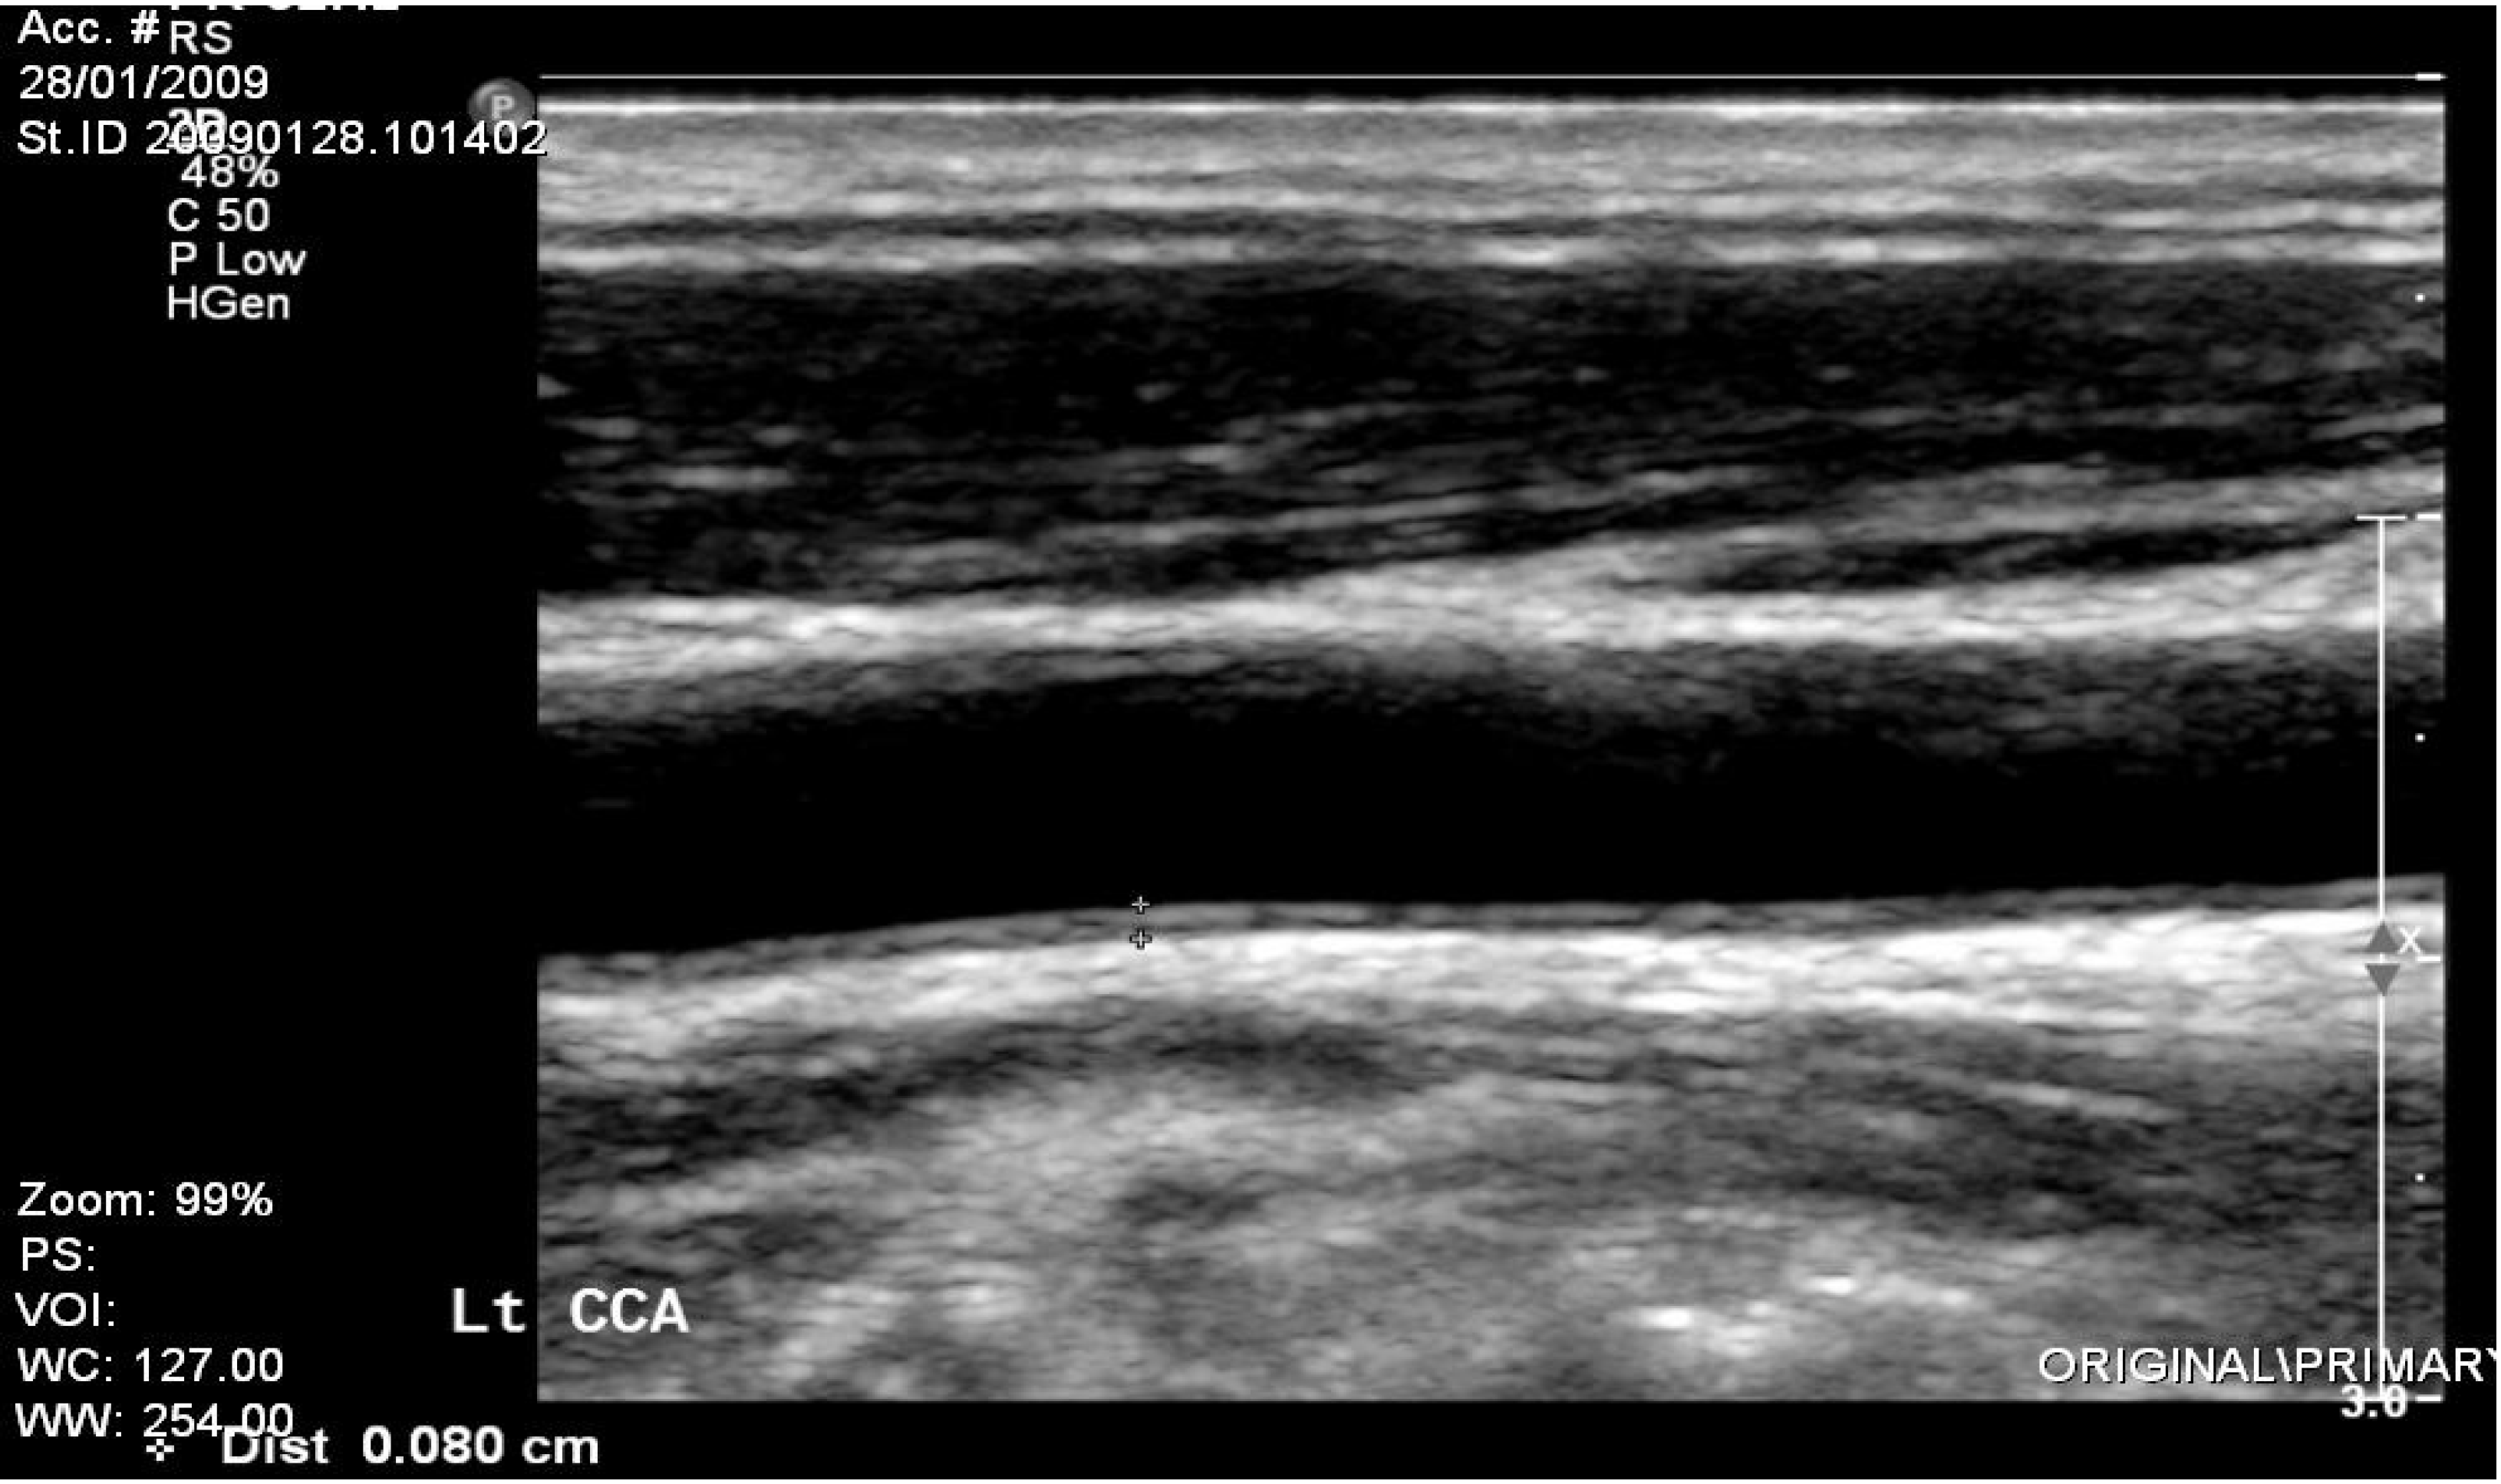

For bilateral assessment of carotid atherosclerosis, all subjects underwent carotid ultrasound for evaluation of intima-media thickness (IMT) and plaques. Carotid scans were acquired using high-resolution ultrasound (Sonos 5500, Agilent Technologies, Palo Alto, CA, USA) and a 10-MHz linear array transducer. Longitudinal views of the left and right common carotid, carotid bifurcations, and internal and external carotid arteries were obtained and recorded on super VHS tapes. All ultrasound studies (carotid and brachial flow-mediated dilation (FMD)) were analyzed off-line by specially trained technicians blinded to other study variables using the prosound system; IMT was measured over 10 mm in the far wall of the common carotid within 2 cm proximal to the bulb. The region with the thickest IMT without focal lesions was measured. Left and right carotid IMTs were averaged. Intima media area in mm2 was defined as: (IMT mm) × (length over which IMT was measured (20 mm)). Plaques were quantified in all carotid segments (common, internal, and external carotid arteries, Figure 4). Plaque was defined as any focal protrusion above the intima [30].

Figure 4.

Example of abnormal intima media thickening (IMT). Normal values of IMT: (age > 50 years; women < 0.7 mm, men < 0.8 mm).

Twenty-nine subjects were diagnosed with NAFLD (without hypertension and without diabetes ) defined by CT (liver minus spleen density ≥ −10 HU), absence of alcohol use (<20 g/day), negative serology for hepatitis B or C diagnosis, negative auto-antibodies, and absence of history of another known liver disease. The control group consisted of 22 gender and age-matched individuals without NAFLD. Intra-observer and inter-observer variability for coronary artery disease (CAD) (stenosis > 50%) was 1% and 5% respectively. Baseline clinical and biochemical characteristics of NAFLD subjects and controls are shown in Table 1. Liver-spleen density was significantly lower in patients with NAFLD than in controls (−15.3 ± 8.9 vs. +6.8 ± 6.7, p < 0.001). The prevalence of smoking was similar among NAFLD patients and controls. Subjects diagnosed with NAFLD had higher triglyceride levels, HOMA values, and waist circumference measurements than controls. All 51 subjects, NAFLD patients and controls, were overweight (BMI 25–30 kg/m2) without statistically significant differences in BMI between the groups (Table 1). Compared with controls, NAFLD patients had a higher percentage of atherosclerotic plaques (70% vs. 30%, p < 0.001), as well as soft plaques (50% vs. 30%, p = 0.001), and greater prevalence of coronary artery disease (30% vs. 15%, p < 0.008), higher right mean IMT, lower retinal artery diameter, and lower AVR (Table 2). After adjustment for possible confounding factors that were identified in univariate analysis, multiple logistic regression analysis demonstrated that NAFLD, IMT, and retinal AVR were strongly associated with CAD, whereas CRP, a biomarker of inflammation was not (Table 3). The association of NAFLD with more severe coronary atherosclerosis remained significant also after adjustment for metabolic syndrome, age, and LDL cholesterol.